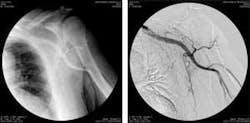

In traditional angiography, images of blood vessels are acquired by exposing the patient to time-controlled x-ray energy while injecting contrast medium into the blood vessels. In this method, the images obtained also record other anatomical structures besides blood vessels. To remove these, mask images consisting of images of the same area without contrast administration are subtracted from sequences of images taken while contrast dye is injected into the patient.

While such applications require high-speed acquisition and processing of long sequences of images, image processing is made more difficult by the movement of the patient and the need to correct for any image distortions. However, the resulting images give doctors a clearer trace of the contrast material’s path through blood vessels.

In the development of its X-Frame CCD digital subtraction angiography (DSA) system, Italray (Florence, Italy; www.italray.it) has used off-the shelf image-processing components to allow DSA to produce images in real time while producing sharper images and lowering radiation dosage to the patient.